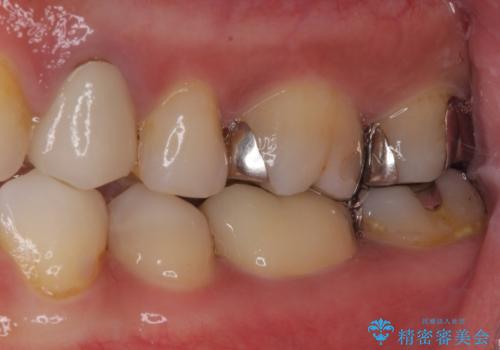

- 奥歯の詰め物や周辺の歯が欠けてしまったとのことで来院された患者様です。

上顎は、元々の詰め物が小さく、欠けた範囲も大きくなかったため、セラミックインレーにて修復治療を行うこととしました。

一方下顎は、元々のむし歯の範囲が広かったため、長期的な予後を踏まえ、セラミッククラウンにて補綴治療を行うこととしました。

特に痛みはありませんでしたが、未然にしっかりとした処置を行うことで、今後むし歯の進行により神経組織が壊死するリスクを低減することが可能となります。